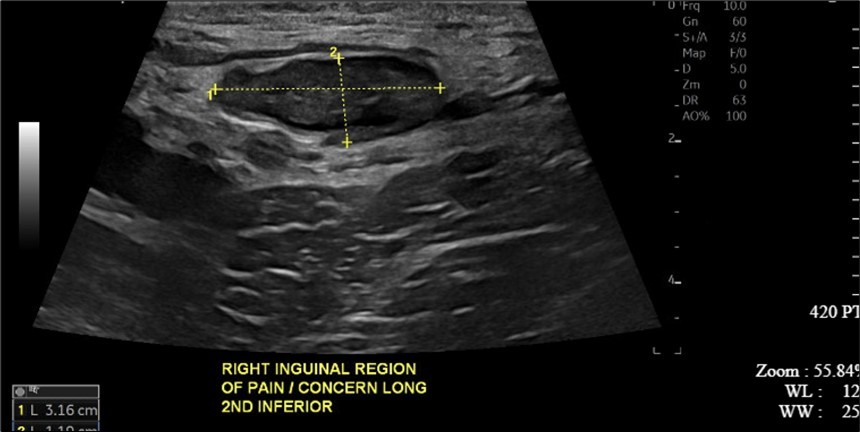

A 34-year-old male presented to the Emergency Department with complaints of large right-sided scrotal swelling, accompanied by scrotal discomfort. The patient’s past medical history was remarkable for a right-sided inguinal hernia, which had been present for several years and was repaired via right open herniorrhaphy with mesh placement three months prior. Physical examination prior to the herniorrhaphy revealed a large inguinoscrotal swelling, measuring 5 inches by 6 inches. During the herniorrhaphy, a very large hernia sac was encountered that could not be fully dissected from the cord structures and required placement of two large meshes; however, the testicles were successfully reduced back into the scrotum. Ultrasound of the right testicle revealed a large hypoechoic space with a complex collection and posterior displacement of the testicle, indicating a possible hydrocele (Figure 1, Figure 2, Figure 3, Figure 4). The patient was taken to the operating room for a right hydrocelectomy. During the procedure, it was noted that the penis was buried within the scrotal swelling, necessitating the placement of a Foley catheter to identify surrounding structures. Upon incision through the Dartos fascia, significant fibrotic tissue and fluid were encountered, making it difficult to maneuver around the hydrocele sac. Upon incising the hydrocele sac, a large collection of thick, dark brown fluid resembling old blood clots was immediately aspirated. Approximately 2 liters of fluid were drained from the sac. After identifying the testicle and cord structures, the proper placement of the testicle within the scrotum was verified. Due to excessive scrotal skin, a scrotoplasty was performed prior to suturing the scrotal skin and fascia (Figure 5). The postoperative hospital course was unremarkable. The patient was discharged with plans to return to the clinic for follow-up with the surgeon.

Figure 2.Ultrasound imaging in the transverse plane of the right testicle.

Figure 3.Ultrasound imaging in the transverse plane of the right inguinal region and underlying soft tissue.